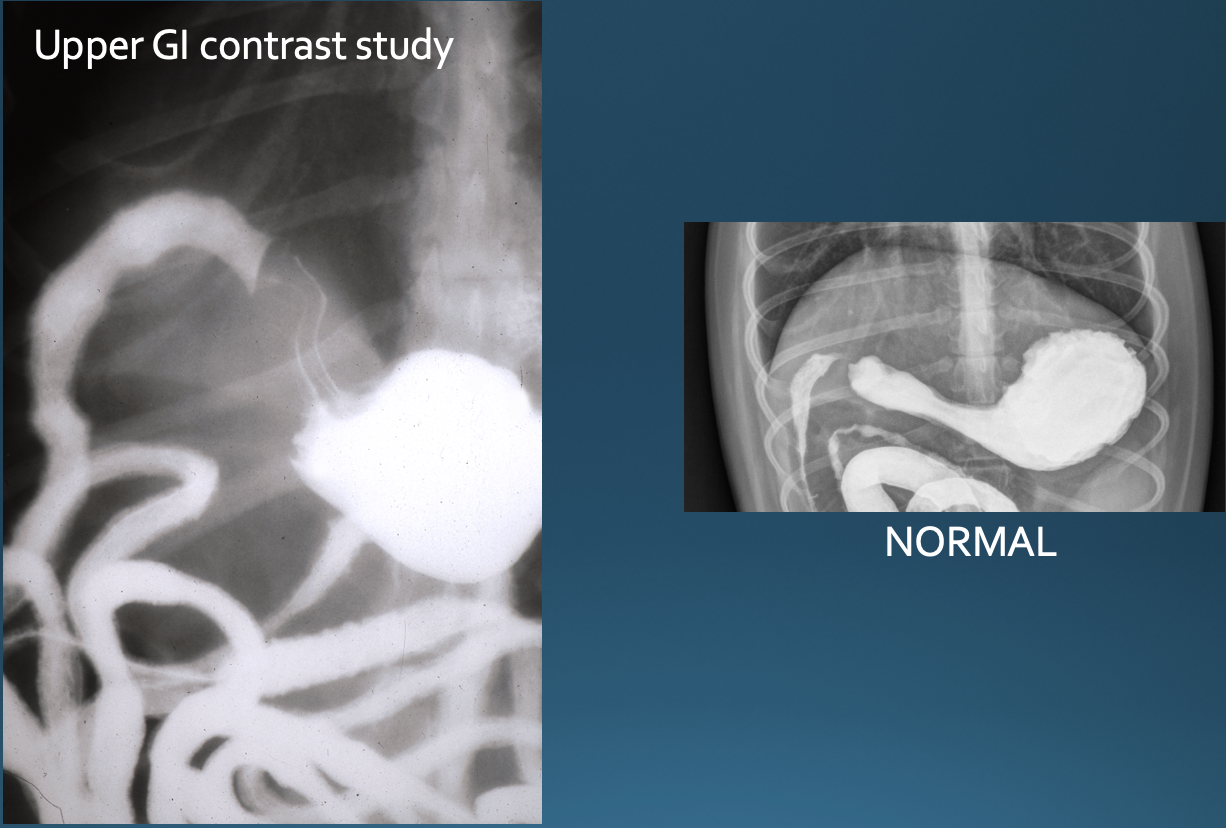

What is shown in these images?

gastric dilatation and volvulus

-“popeye arm” or “smurf hat”

-pylorus has moved dorsally and cranially; not seen well on VD view

-compartmentalization band seen

-pylorus is gas-filled on right lateral view